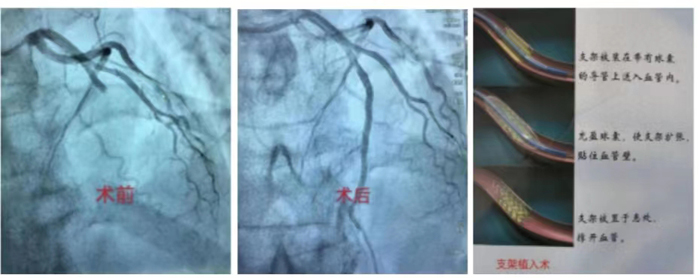

冠心病介入診療技術:科室常規(guī)開展冠狀動脈造影術、經皮冠狀動脈球囊擴張術(PTCA)、經皮冠狀動脈藥物球囊擴張術,振波球囊技術治療冠脈嚴重鈣化病變、冠狀動脈支架置入術、心臟血管內超聲檢查(IVUS)、血流儲備分數測定(FFR)、冠狀動脈旋磨成形術等介入手術。在冠脈左主干、分叉病變、慢性完全性堵塞性病變、彌漫性及鈣化病變等復雜病變方面積累了豐富的經驗。胸痛中心針對急性心肌梗死患者開通綠色通道,其中急診冠心病介入診療技術為棗莊地區(qū)開展最早,挽救急性心肌梗死病人最多的科室。

急診PCI術:是指在患者發(fā)生急性心肌梗塞后12小時內進行的冠狀動脈血運重建,患者首先在導管室行冠狀動脈造影術,找出冠狀動脈“罪犯”血管及其病變部位,對病變部位行經皮冠狀動脈腔內成形術和植入支架,使閉塞的血管得以再通,梗死相關心肌得以及早的再灌注和功能恢復??梢哉f,急診PCI術為挽救急性心梗垂危的生命在最短的時間內構建了一條綠色的通道,提高危重癥患者的搶救成功,使急性心肌梗死的死亡率下降,提高患者的生活質量。因此,在急性心肌梗死的時間窗內,介入治療已是首選治療手段,其急診PCI大大降低死亡率及心肌梗死并發(fā)癥,提高生存率及改善生活質量。